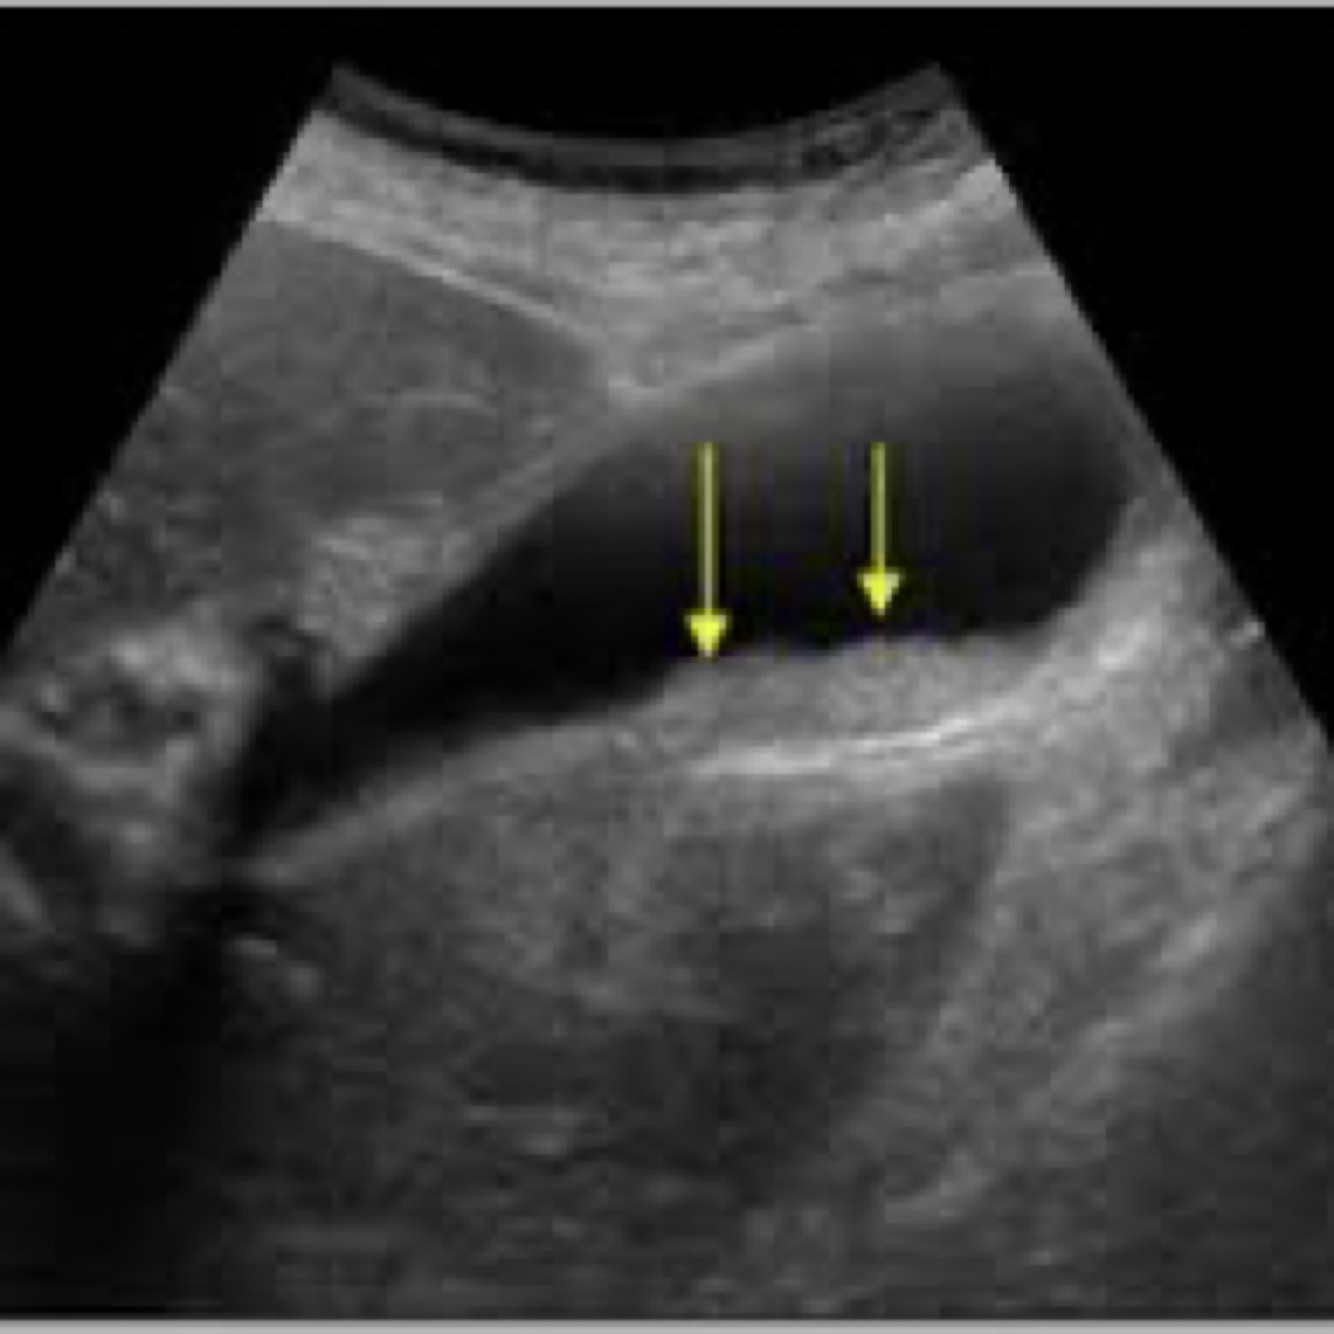

Aka parallel channel sign, representing dilated duct running anterior to its accompanying portal vein or hepatic artery. Irregular jagged, walls and branching patterns of ducts, compared to smooth walls and smooth verifications of portal venus system. Stellated confluence of dilated ducts converging toward the porta hepatis.

Double-barreled shotgun

56

Double barrel shotgun